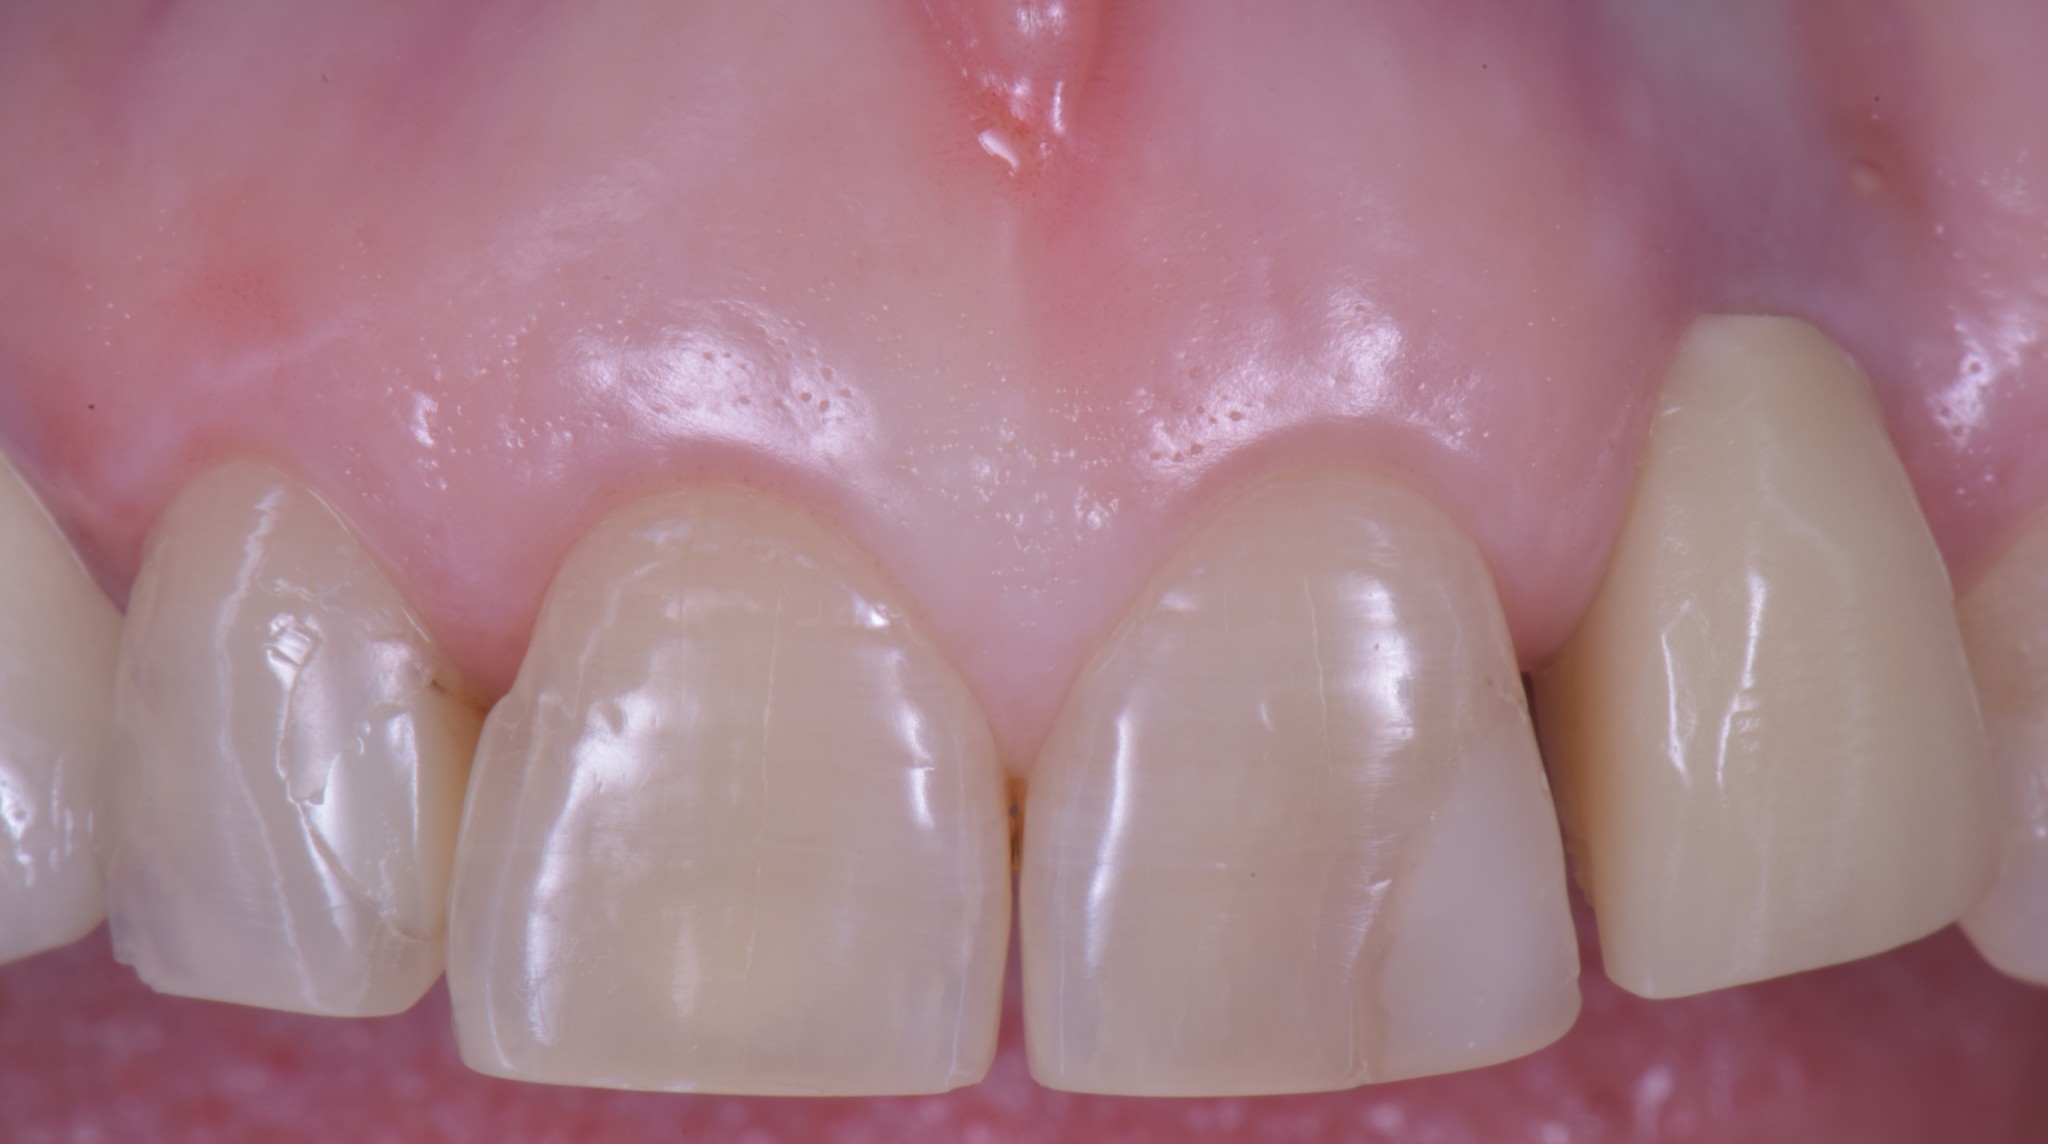

Un dente su impianto oggi ha la possibilità di avere questo aspetto

O questo, se vuoi un esempio frontale.

Soprattutto se si parte da una condizione tissutale ottimale.

Come puoi vedere abbiamo risolto completamente il deficit dei tessuti molli che era stato lasciato dopo le precedenti terapie e…

… posto le basi per una nuova riabilitazione definitiva che si possa definire esteticamente degna dei tempi in cui abbiamo la fortuna di vivere.